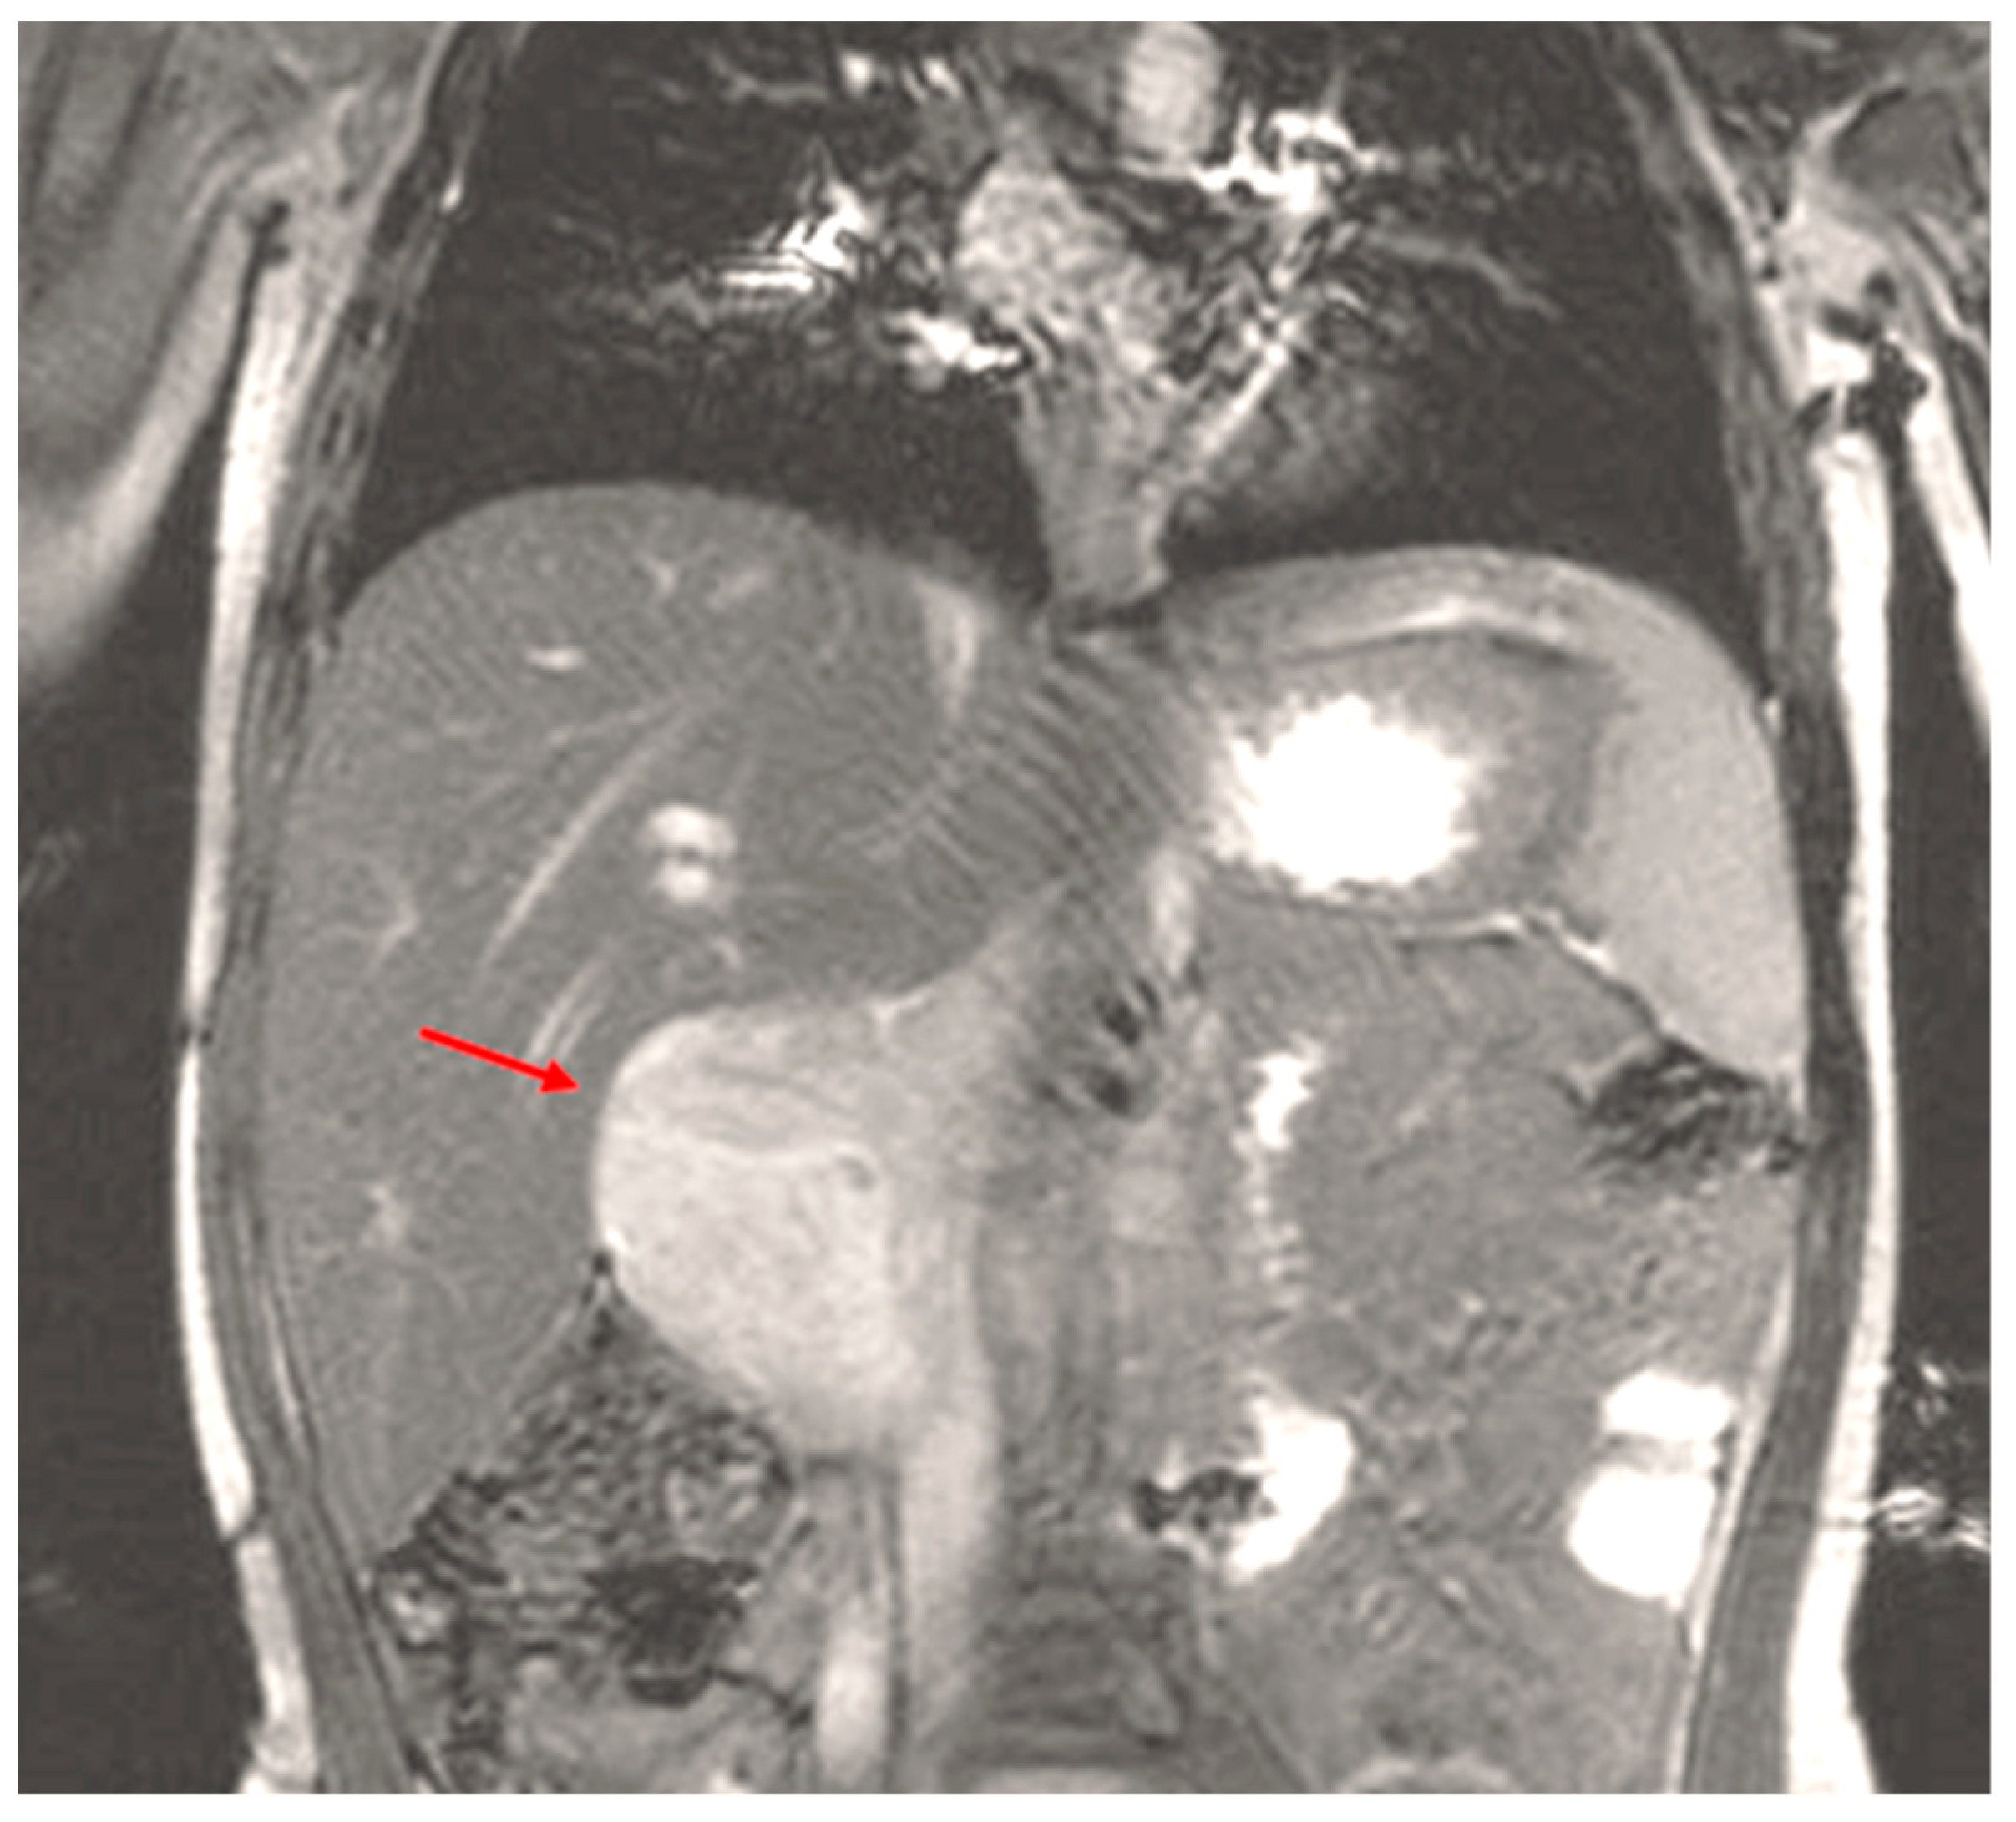

3. Presentation

4. Assessment

14. Assessment